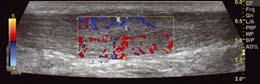

zwyrodnieniowa stawu skokowo-goleniowego

Zmiany w stawach stopy w przebiegu reumatoidalnego zapalenia

Staw skokowy dolny